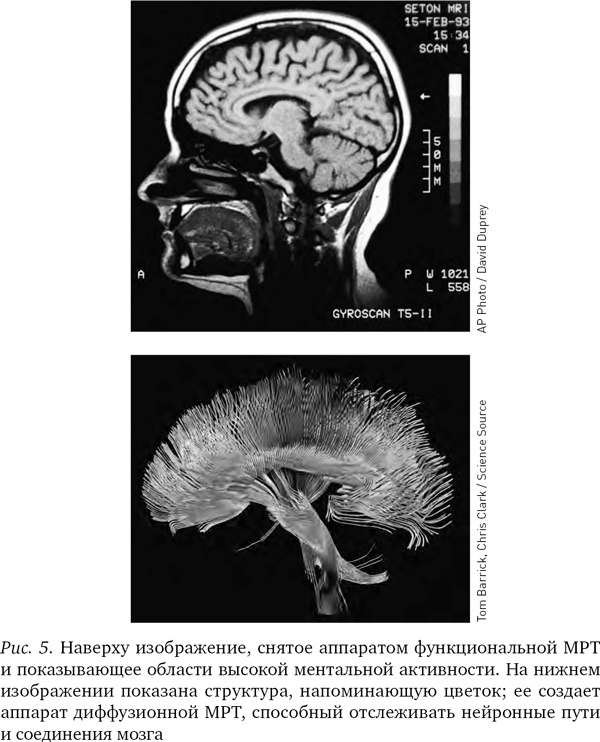

Различные химические элементы реагируют на разные частоты радиоволн по-разному, поэтому мы можем, изменяя частоту волны, определять, где какие элементы находятся. Как уже отмечалось, при фМРТ в основном отслеживаются атомы кислорода в крови и измеряют кровоток, но вообще-то аппарат МРТ можно настроить на любое вещество. В последнее десятилетие появилась новая разновидность МРТ — диффузионно-тензорная; она отслеживает движение воды в объеме мозга. Вода в мозге следует по нейронным путям, поэтому диффузионно-тензорная томография позволяет получить красивые картинки, напоминающие переплетение растущих в саду лиан. Теперь ученые могут мгновенно определить, как части мозга связаны между собой.

Иллюстрация к книге — Будущее разума [i_005.jpg]